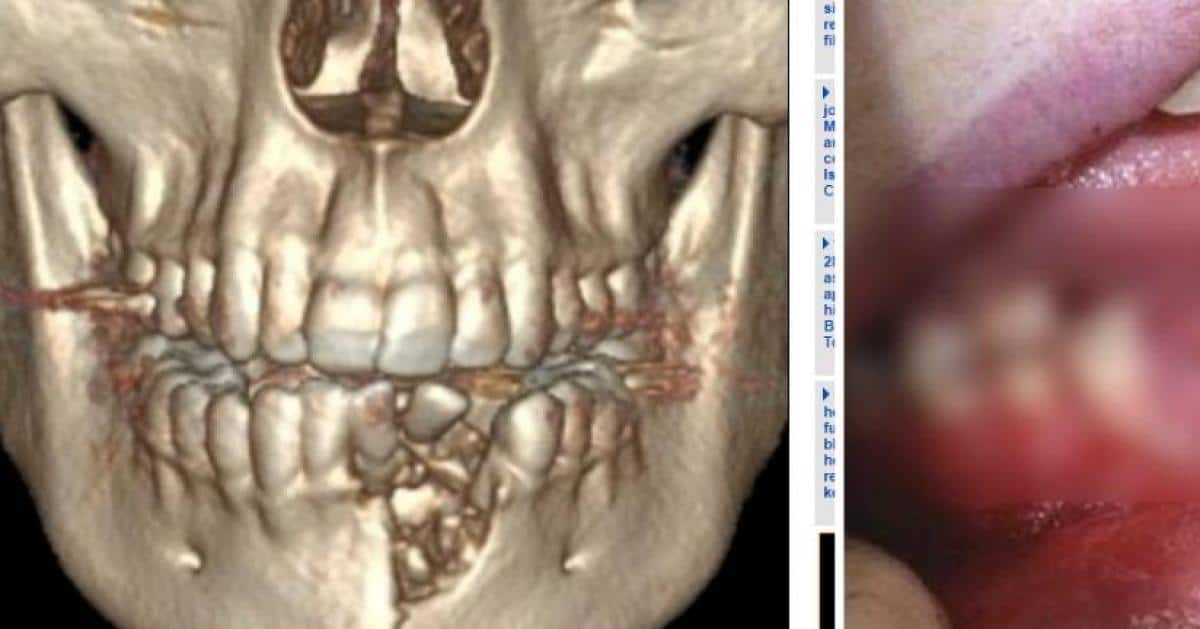

Sa mâchoire explose

Depuis quelque temps, l'adolescent de 17 ans, Austin Adams, avait décidé d'arrêter de fumer. Afin de l'aider dans son combat, sa mère lui avait acheté une cigarette électronique. Malheureusement, il a été victime d'un grave accident avec ce nouvel ustensile. Celle-ci a explosé dans sa bouche à cause de la pile qui avait surchauffé. On vous parlait également du jeune homme tué par l'explosion de sa cigarette électronique. Il a immédiatement été emmené dans un établissement spécialisé pour que l'on soigne ses blessures et ses brûlures. Il a été pris en charge par la chirurgienne Katie Russell. "Il a dû subir une réduction ouverte et une fixation interne de la fracture, une extraction dentaire et un débridement de tissu dévitalisé" a-t-elle expliqué.

Pendant 6 semaines, Austin n'a pas pu ouvrir la bouche et a dû se nourrir exclusivement d'aliments liquides et de purée. Sa mâchoire a été brisée et quelques dents ont été cassées. Ce n'est malheureusement pas le premier accident causé par une cigarette électronique. En effet, l'an dernier, un homme est décédé en Floride à cause d'une cigarette électronique. D'autres personnes ont également été blessées. Il faut donc rester prudent afin de limiter les accidents. On espère qu'Austin se rétablira vite.